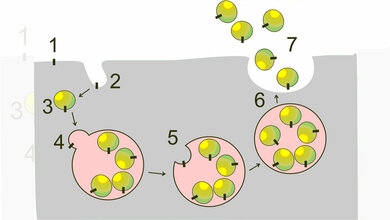

Der Bluttest basiert auf der EDIM-Technologie. Sie beruht darauf, dass Makrophagen durch den Körper „patrouillieren“ und dabei ungewünschte Zellstrukturen, wie beispielsweise Bakterien, Viren oder eben auch entartete körpereigene Zellen, aufnehmen. Bei der EDIM-Technologie ist es das Ziel, diese „gefressenen“ Zellstrukturen – im Falle des PanTum Detect durch die Biomarker TKTL1 und Apo10, die charakteristisch sind für solide Tumore – im Innern der Makrophagen nachgewiesen werden. Dafür bedarf es lediglich einer einfachen Blutprobe.

Mit der Detektionstechnologie von EDIM soll so das körpereigene Immunsystem zum Indikator für Tumorentwicklungen werden. Das Immunsystem ist evolutionär dazu ausgebildet, im Körper entartete Zellen und körperfremde Zellen aufzuspüren und zu phagozytieren. Diese Vorgänge erfolgen hochspezifisch, da Makrophagen die Zellen nur dann fressen, wenn diese sie als entartet erkennen. Deshalb ist laut Zyagnum die Problematik falsch positiver (und auch falsch negativer) Ergebnisse dabei äußerst gering: Der PanTum Detect soll Tumore mit einer Sensitivität von 97,5 Prozent bei einer Spezifität von 99,53 Prozent nachweisen. Das heißt, 97,5 Prozent aller Tumore sollen mit dem Test detektiert werden, und nur einer von 200 gesunden Patienten würde dann als falsch positiv erkannt.

Der Test nutzt die Biomarker TKTL1 und Apo10, welche fundamentale biophysikalische Prozesse nachweisen, die in jedem soliden Tumor, unabhängig der Entität, vorkommen. Nachgewiesen wurde ein Zusammenhang bereits für über 40 Tumorarten, unter anderem Prostatakarzinom, Ösophagus-Karzinom, Schilddrüsenkrebs, Kolon-Karzinom, Magenkrebs, Brustkrebs, Ovarialkarzinom, Glioblastome und Bronchialkarzinome, so der Hersteller und verweist auf zahlreiche Studien. Dass der Test einfach durchzuführen, für den Patienten ungefährlich und zusätzlich kostengünstig ist, ermögliche im Gegensatz zu anderen empfohlenen Screeningverfahren eine jährliche Durchführung des Tests. Einmal im Jahr durchgeführt, erhöhe PanTum Detect somit die Wahrscheinlichkeit, einen Tumor rechtzeitig zu entdecken und erfolgreich behandeln zu können.